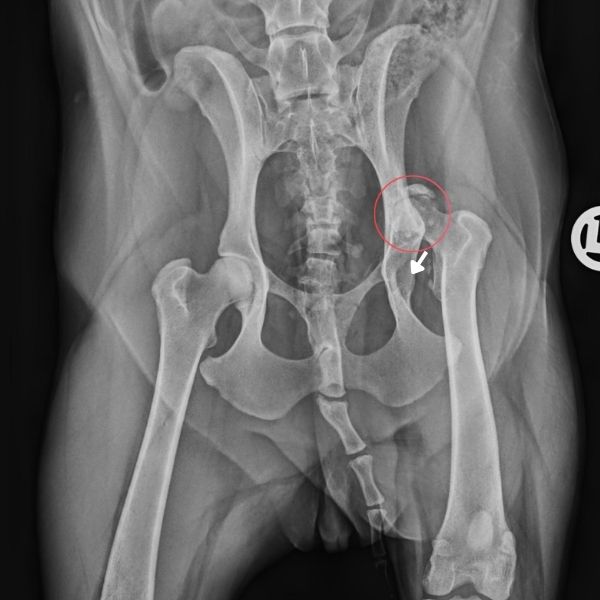

Eine Röntgenaufnahme zeigt, was bei Zedra für den unrunden Gang sorgt:

Zu Beginn war ihre rechte Hüfte luxiert. Das bedeutet, dass der Gelenkkopf des Oberschenkels nicht mehr korrekt in der Gelenkpfanne saß. Im Laufe der Zeit hat der Körper auf diese Fehlstellung reagiert: Der Oberschenkelkopf ist nicht einfach nur „rausgerutscht“, sondern seitlich an der Hüfte festgewachsen. Dadurch hat sich dort ein sogenanntes Pseudogelenk gebildet – also eine Art Ersatzgelenk, das der Körper selbst geschaffen hat, um mit der Situation irgendwie zurechtzukommen.

Röntgenbild von Zedras Hüfte. Zu sehen ist auf der rechten Seite, dass der Gelenkkopf des Oberschenkels nicht mehr in der Gelenkpfanne sitzt. Er ist an der Seite der Hüfte angewachsen.